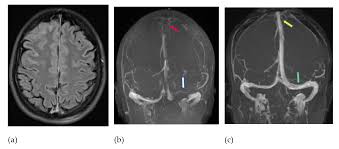

先日、モデナの遺伝子ワクチン接種5〜10日後に脳血栓(脳静脈洞血栓)、肺塞栓、両下肢深部静脈血栓で亡くなった症例報告論文が出ました(Thrombosis With Thrombocytopenia After the Messenger RNA-1273 Vaccine. Ann Intern Med. 2021 Jun 29. doi: 10.7326/L21-0244)。

とくに新型コロナ遺伝子ワクチンで起こりやすいとされているのが、脳血栓症ですが、ファイザー、モデナとアストラゼネカの接種による発症率はほぼ同じです(Cerebral venous thrombosisand portal vein thrombosis: a retrospective cohort study of 537,913COVID-19 cases. DOI 10.17605/OSF.IO/H2MT7( Last Updated: 2021-04-27))。